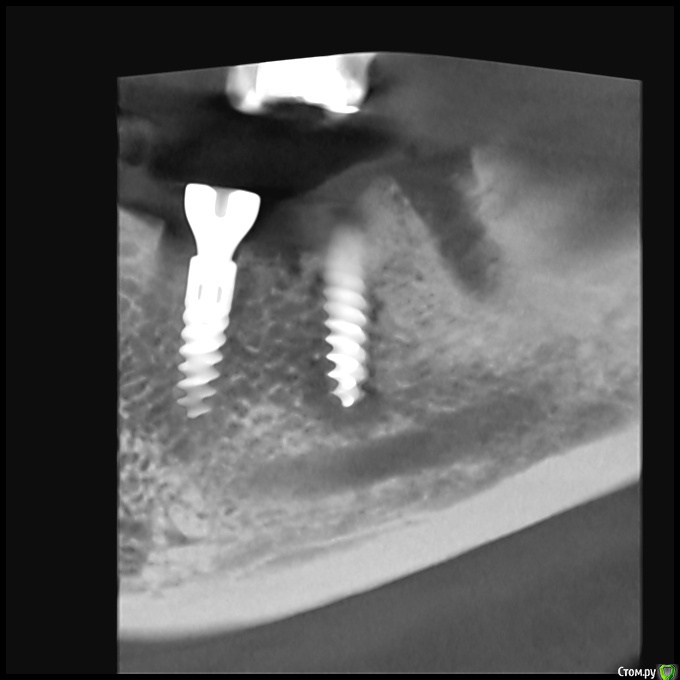

Local Опубликовано 4 января, 2020 Автор Поделиться Опубликовано 4 января, 2020 (изменено) Такой подойдёт? Если неинформативно, выложу другой. Изменено 4 января, 2020 пользователем Local Ссылка на комментарий

Local Опубликовано 3 января, 2020 Автор Поделиться Опубликовано 3 января, 2020 (изменено) Был на приёме.По результатам прицельной КТ хирург сказал, что между позициями 45,46 (там, где стоят импланты) образовался карман и протекает воспалительный процесс. Предположительно из-за подсыпанного в процессе имплантации костного(?) материала.Выкрутил формирователь в позиции 45, разрезал десну, почистил карман, удалил часть материала, поставил коллагеновую мембрану, зашил и снова вкрутил формирователь.Через 2 дня на осмотр. Изменено 3 января, 2020 пользователем Local Ссылка на комментарий

red_butler Опубликовано 3 января, 2020 Поделиться Опубликовано 3 января, 2020 Покажите срезы Кт Ссылка на комментарий